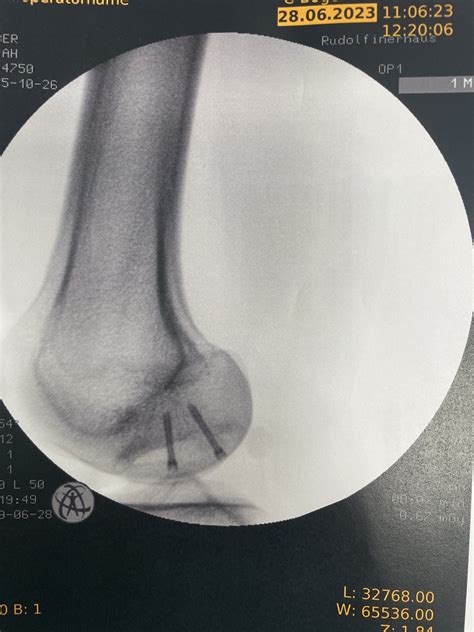

What is osteochondritis? Osteochondritis is a condition where a small section of bone and cartilage in the knee weakens and separates from the rest of the joint. This can cause pain, swelling, and even. Aug 11, 2025 · Osteochondritis Dissecans is a pathologic lesion affecting articular cartilage and subchondral bone with variable clinical patterns. Diagnosis may be made radiographically (notch. Osteochondritis dissecans affects joints, most frequently the knee, in children and adolescents. It can also affect other joints, such as elbows and ankles. This condition occurs when a piece at the end of. Oct 14, 2024 · Osteochondritis dissecans happens when a section of bone in one of your joints loses its blood supply and becomes soft and weak. Even though experts aren’t sure what causes it, your.

Osteochondritis dissecans | Orthopedist Vienna